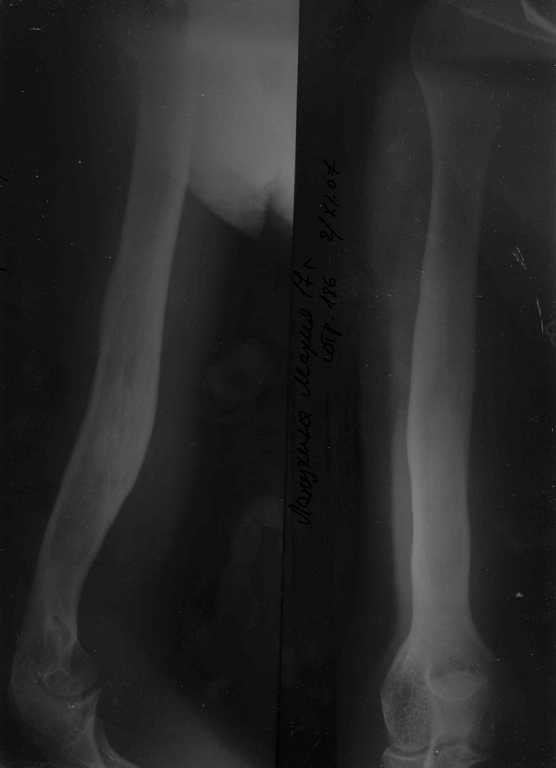

Уважаемые коллеги!Обратившаяся на консультацию девушка была оперирована 8 лет назад в нашей больнице по поводу рецидивирующей аневризмальной кисты плечевой кости. К сожалению, по ряду причин, сейчас невозможно представить исходные снимки. Киста располагалась а ср/з и н/з плечевой кости. В конечном итоге ребёнок был оперирован. Выполнена экскохлеация кисты, замещение полости аллотрансплантатами из кортикальной кости. После наблюдения в течение 10 месяцев больная перестала появляться и считала себя здоровой. Соблюдала и соблюдает охранительный режим, иногда играет в бадминтон. Укорочение больного плеча 2,0 см. Смежные суставы имеют полный объём движений и т.д. На выполненной в начале ноября сего года рентгенограмме (сразу прошу прощения - может быть не очень хорошо видно) в дистальном метадиафизарном отделе прослеживается остаточная полость при, вроде бы, неплохом состоянии кортикального слоя. Девушка, естественно, вовсе не заинтересована в развёрнутом обследовании, крайне загружена учёбой и делами. Болезненно реагирует при одной мысли о медицинском вмешательстве.Само наличие и локализация остаточной полости конечно же не радует.Вопрос. Опасна ли эта остаточная полость при ведении обычного образа жизни для прочности плечевой кости? Есть ли необходимость в дополнительном исследовании (КТ, кистография)для определения дальнейших действий с этой полостью и надо ли с ней вообще что-либо делать (малоинвазивно или "многоинвазивно"? С уважением. Заранее спасибо за помощь.